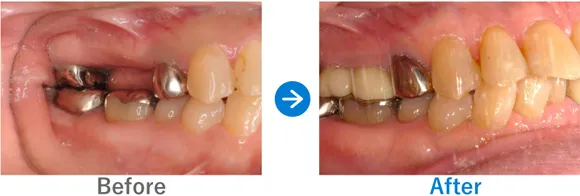

Case2

ブリッジで歯根が破折。セカンドオピニオンにより低コストで治療できた

左下6のブリッジ破折

インプラント1本:左下6、抜歯テルプラグ

396,000円(内訳:抜歯テルプラグ、インプラント1本(ストローマン)、ガイド、仮歯、保証20年)

来院の背景

ブリッジ治療を受けていた歯の根っこが破折してしまい、かかりつけ医院でインプラントを提案されたそう。かかりつけ医では骨の治療が必要だと言われ、インプラント自体の費用も高額だったため、セカンドオピニオンで来院されました。

治療結果

骨の幅がじゅうぶんにあったため、骨の治療は行わずにインプラントを埋入。しっかり噛めるようになりました。現在は他の歯も治療中です。

喫煙されているため、インプラント周囲炎にはとくに注意が必要です。定期的なメンテナンスが重要です。